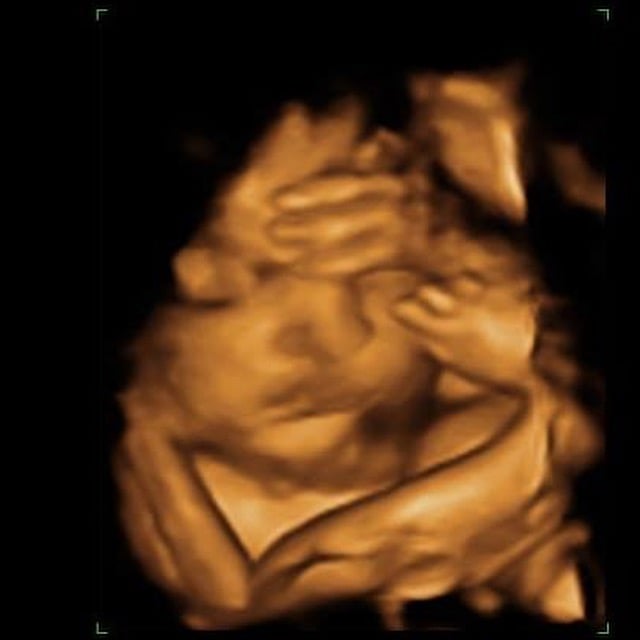

• I LOVE the 3d/4d :( the benefit is that most of the time of you do not get a good session most places Ive gone give second sessions free of charge. Ive done it with both my boys. :) my first born on left and 2Nd on right :)